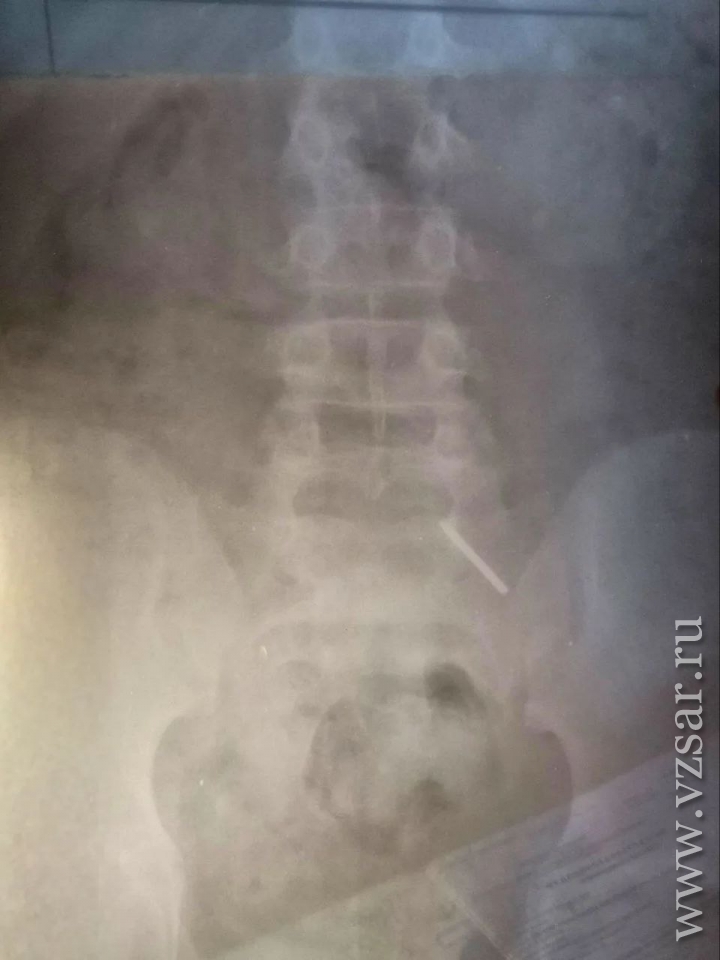

В Балаковской городской клинической больнице (Саратовская область) врачи спасли ребенка, проглотившего инородный предмет, сообщает тг-канал медучреждения.

В клинику поступил 11-летний школьник, который, как оказалось, проглотил часть циркуля.

"Эндоскопически достать предмет не представлялось возможным из-за позднего обращения пациента. Главной задачей было не допустить перфорации кишечника и кровотечения - мальчик находился под наблюдением врачей и рентгенологов. В итоге инородное тело вышло естественным путем. Пациент выписан домой", - рассказали в больнице.